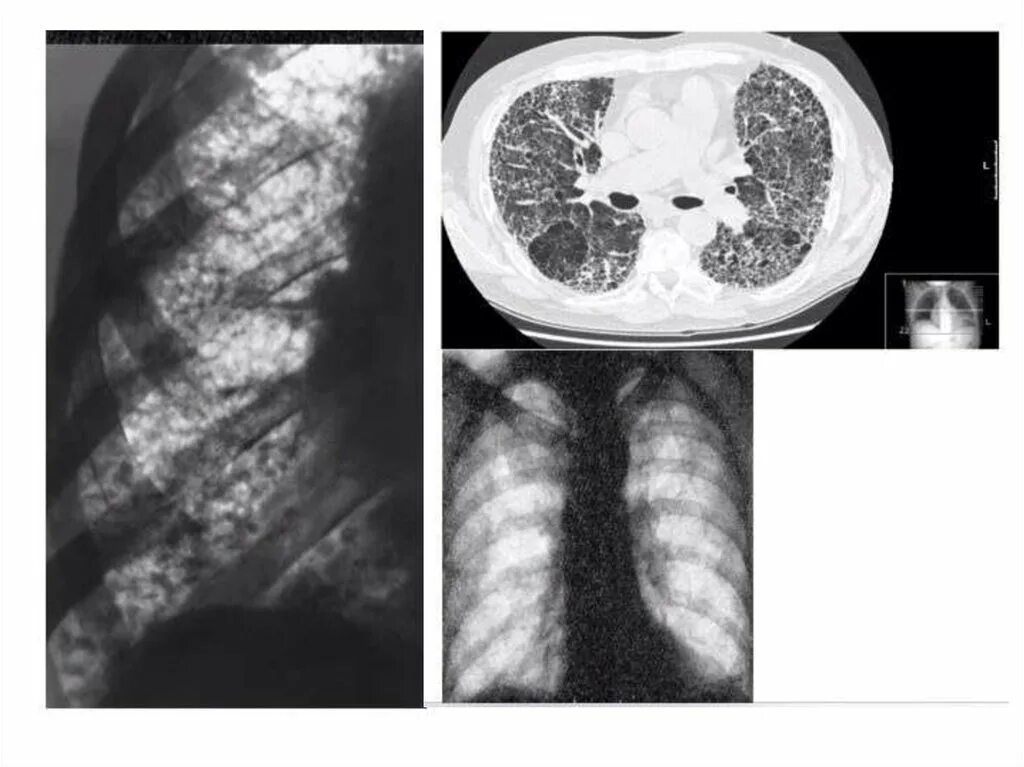

Диффузную системную склеродермию